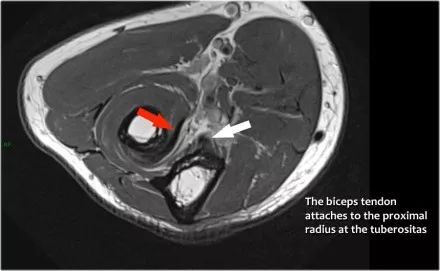

二头肌腱:从肌腱连接处到径向结节上的附着物。

● 远端肱二头肌肌腱撕裂:有完全撕裂,因为如果我们一直跟随肌腱进入桡骨结节,我们可以看到肌腱不附着在那里(绿色箭头)。只有流体。● 肌腱不缩回的原因是因为广泛的萎缩性肌腱 - 也被称为lacertus fibrosus - 仍然完好无损(红色箭头)。● 远端肱二头肌肌腱不仅插入到桡骨结节,而且还通过褶皱纤维进入前臂内侧屈肌旋前肌块的筋膜。

下面是另一种情况。在矢状图像上,我们不确定可能的撕裂。也许只有一些肌腱炎或肌腱炎。轴向图像显示部分撕裂(红色箭头)。

始终确保你的轴向扫描一直到结节,因为你太早停止,就像在这种情况下,你只会看到增厚的肌腱和一些液体,但你不确定可能的撕裂。

3.桡骨肱二头肌的滑囊炎桡骨肱二头肌的滑囊炎Radiobicipital bursitis

以下是患者的矢状和轴向图像,该患者被转诊给整形外科肿瘤外科医生,用于肘部附近的肿块。肱二头肌肌腱有部分撕裂(箭头),该结构是桡骨肱二头肌的囊,所以这是一个滑囊炎。

请记住,肱二头肌肌腱没有腱鞘,因此腱鞘炎是不可能的。